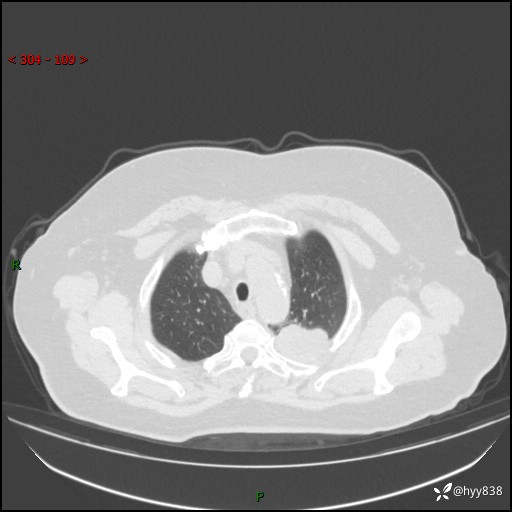

老年女性,左上肺结节8年。典型又不典型,看你如何解读---结果公布(值得分析)

主诉:检查发现左上肺结节8年,较前增大。

简要病史:患者于8年前体检行胸部CT检查发现左上肺结节(4mm),患者平素间断咳嗽咳痰,无心慌、胸闷、胸痛、呼吸困难、低热、盗汗,无头痛、头晕,无腹痛、腹胀等不适,未行特殊处理,定期复查。2023-09-21胸部CT示左上肺结节(2cm)较前增大,2024-02-01胸部CT示左上肺尖后段(39*32mm),左侧肺门及纵隔淋巴结增大,现患者欲求手术治疗,遂来我院就诊,以“左上肺结节”收入我科。 患者自起病以来,精神可,睡眠可,饮食可,大小便正常,体重无明显改变。

辅助检查:CT

胸部CT平扫